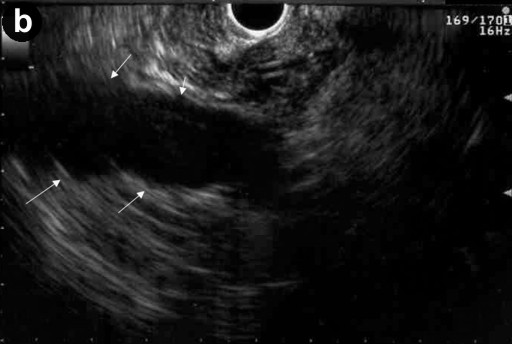

A 57-year-old man with a one year history of alcohol-induced chronic pancreatitis presented with a 1-month history of intermittent epigastric pain. He denied any associated nausea, vomiting, diarrhea, weight loss or other gastrointestinal symptoms. His past medical history was significant for hypertension, type 2 diabetes mellitus, dyslipidemia and chronic obstructive pulmonary disease. The abdomen was soft and non-tender. The liver and spleen were not felt, and no abdominal mass was appreciated. His physical examination was otherwise unremarkable. Laboratory evaluation revealed serum amylase of 356 U/L (reference range: 30-111 U/L) and a lipase of 679 U/L (reference range: 46-218 U/L). Complete blood counts, liver chemistries, carbohydrate antigen 19-9, and alpha-feto protein levels were all normal. Pancreas protocol CT scan of the abdomen revealed a 8x5 cm cystic fluid collection in the left liver lobe, an L-shaped subcapsular fluid collection inferior to right hepatic lobe 10x9 cm in size and a 2.4 cm complex fluid accumulation that involved the head and the superior aspect of the body of pancreas (Figure 1). CT guided diagnostic aspiration of the hepatic cystic lesion drained 100 mL of straw-colored fluid which showed no organisms on gram stain and was sterile on bacterial and fungal cultures. Cytological examination of the fluid did not reveal any malignant cells. The amylase level in this fluid was greater than 51,065 U/L which confirmed the diagnosis of intrahepatic pancreatic pseudocyst extension. At the time of CT guided aspiration, the pseudocyst was treated with percutaneous drainage with the placement of an 8F pig-tail catheter. The intrahepatic pancreatic pseudocyst extension failed to resolve even after 4 weeks of the pig-tail catheter placement (Figure 2). At this point, an ERCP was performed which revealed a normal cholangiogram. Pancreatography revealed a normal-appearing main pancreatic duct to the region of the pancreatic neck, and a ductal stenosis 12 mm in length was identified beginning at the pancreatic body near the neck. The main pancreatic duct and pancreatic duct branches were dilated upstream of the stenosis to about 7 mm (Figure 3). After performing an 8 mm ventral pancreatic sphincterotomy; the stricture was dilated with a 6 mm biliary dilating balloon and a 7F, 10 cm long pancreatic stent was inserted to the tail (Figure 4). Brush cytology and intraductal biopsy specimens were obtained from the stricture and revealed fibrosis and changes of chronic pancreatitis; they were negative for malignancy. EUS examination revealed a pancreatic head cystic lesion extending into the left hepatic lobe (Figure 5ab); fluid examination revealed an amylase of 54,450 U/L and the cytology was negative for malignancy. A follow-up pancreas protocol CT of the abdomen 6 weeks later revealed complete resolution of the pancreatic head fluid accumulation and the intrahepatic pancreatic pseudocyst and decrease in size of the L-shaped subcapsular fluid collection to 2x4 cm (Figure 6). Percutaneous drainage of the remaining L-shaped subcapsular fluid collection was discussed with the patient but he refused any percutaneous or surgical drainage. A follow-up pancreatogram revealed marked improvement in the pancreatic duct stricture. He remains asymptomatic after 9 months of follow-up.

Figure 5. a. EUS showing the pancreatic head cystic lesion. b. Cystic lesion extension into the left hepatic lobe. |